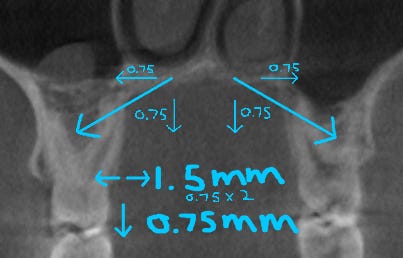

The below diagram illustrates the amount of vertical change relative to transverse expansion with MARPE.

The actual vector of expansion (the real direction of the skeletal motion) seems to be about 45 degrees downward, which certainly could vary depending on device design and resistance forces (like the ones Dr. Manuele mentioned), i.e. where the device is placed, as well as the age of the patient.

So, if the amount of turns sums to 1.5mm, then the downward vertical gain could be roughly 0.75mm under this ratio.